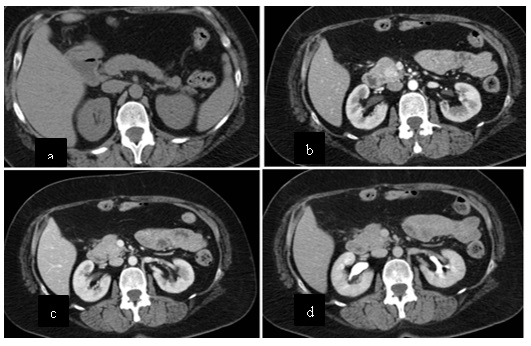

Caso 2

Paciente femenina de 48 años de edad que ingresa a Hospital Sanatorio Franchin por síntomas de cefalea y mareos, cuadro que se hace progresivo, presentando síncopes y posteriormente alteración del estado de conciencia. Los exámenes clínicos revelan una glucosa de 40 mg/dl, concomitante con insulina alta y péptido C elevado. Ingresa de forma programada para realización de duodeno pancreatectomía el 29 de mayo de 2021. Imágenes diagnósticas muestran estudio trifásico de tomografía de abdomen, lesión nodular en la cabeza del páncreas con ávido realce en fase arterial que en resonancia magnética se observa hiperintensa en T2, presenta restricción con la difusión y caída de la señal en el ADC. Además presenta realce tras la administración de contraste con gadolinio.

Estudio histopatológico reveló tumor neuroendocrino bien diferenciado grado 1.